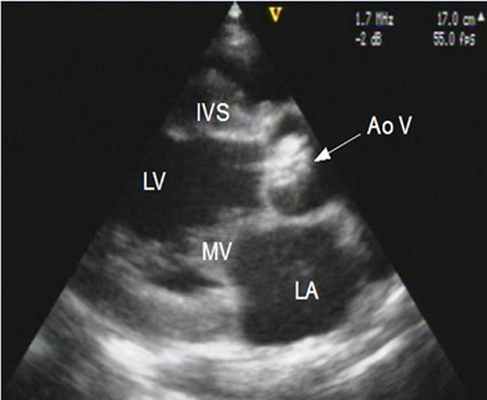

Эхокардиография при митральном стенозе

Причиной стеноза митрального клапана обычно является ревматизм. Редко стеноз МК может быть врожденным, связанным с дегенеративной кальцификацией, гиперэозипофилией, инфекционным эндокардитом, влиянием радиации и лекарственных препаратов. Типичные признаки ревматического стеноза МК можно обнаружить при ЭхоКГ в М- и В-режимах. Площадь отверстия МК измеряют планиметрически в парастернальной позиции по короткой оси. Трехмерная ЭхоКГ позволяет лучше определить площадь отверстия клапана у больных со стенозом МК или у перенесших комиссуротомию.

4. Эхокардиография (УЗИ-сердца) - является основным методом диагностики и оценки прогноза больных с аортальным стенозом. При этом возможна визуализация структур корня аорты и выносящего тракта левого желудочка, оценка подвижности створок и их состояния, определение локализации стеноза.

В норме площадь отверстия аортального клапана у взрослого составляет 3-4 см2, хотя имеются отклонения от этого показателя в зависимости от размеров тела пациента.